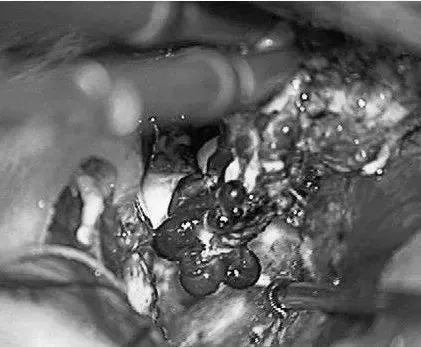

患者案例2:17岁男孩,表现为来自于右侧胼胝体压部AVM的脑室内出血(补充Spetzler-Martin分级4级:S1V1E1/A1B0C0),SplenA供血,SplenV和内侧AtrV引流右椎动脉造影。

手术步骤图解

(a)侧位(b)前后位].(c)他取侧卧位,右侧朝下,鼻朝下,中线取水平位以便靠重力牵拉右侧枕叶。窦汇开颅,显露SSS、TrvS、枕较、后纵裂和镰幕交界处。SplenA沿胼胝体压部上升,顺着它可达AVM(续)。